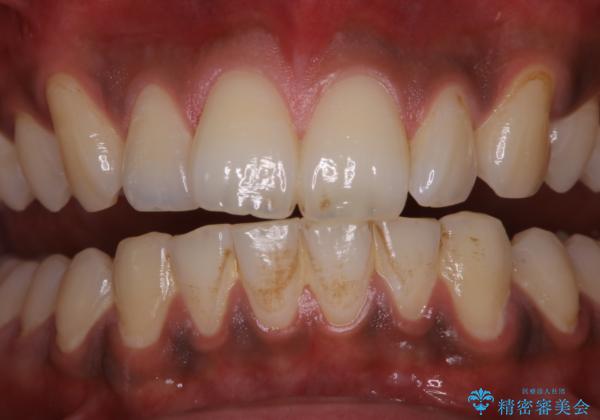

歯についたタバコのヤニをPMTCで綺麗に

- 電子タバコを吸う習慣があり、ステインがついてしまっている見た目が気になるとのことで来院されました。ステインだけではなく、歯石も全体的に付着していたためPMTC60分コースを行いました。

PMTCは、歯に付着した汚れを除去していくため、着色が気になる場合にも行うことができます。ご自身でのセルフケアだけで着色を落とそうとすると、逆に歯を傷つけてしまったり、精密に汚れを除去できないこともあります。また、日常生活で着色しやすい飲食物を避けたりすることはストレスに感じてしまったり、あまり現実的ではありません。